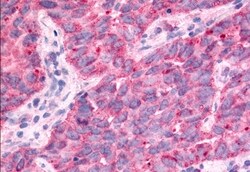

TAOK1 Polyclonal Antibody for IHC (P)

| Immunohistochemistry (Paraffin) | |